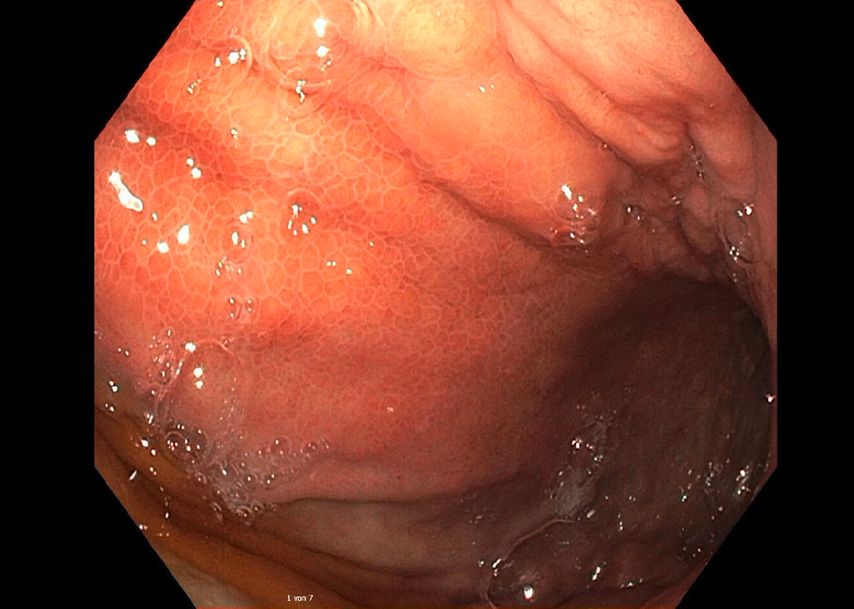

In der durchgeführten Computertomografie des Abdomens (Abb.1) zeigt sich der Verdacht auf einen hohen Ileus mit prall sekretgefülltem, distendiertem Magen (25cm kraniokaudal). Weiters stellt sich die Magenwand auf bis zu 17mm verdickt dar – mit intramuralen Lufteinschlüssen, insbesondere entlang der großen Kurvatur. Eine Ausgangsstenose im gastroduodenalen Übergang wird suspiziert. Rasch wird eine nasogastrale Sonde eingebracht, die trotz korrekter Lage kein Sekret fördert.

Eine Gastroskopie unter Intubationsnarkose wird angeschlossen (Abb.2). Gastroskopisch ist der Magen leer, die Schleimhaut adäquat durchblutet, ohne Ulzerationen oder malignomsuspekte Areale. Die einzige Auffälligkeit: Der Magen entfaltet sich nicht gänzlich, und zwar aufgrund einer submukös liegenden, verdrängenden Raumforderung im Bereich der Magenvorderwand. Aufgrund der Raumforderung kann der Pylorus nicht eingesehen werden.